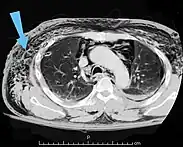

Significant cases of subcutaneous emphysema are easy to diagnose because of the characteristic signs of the condition.[1] In some cases, the signs are subtle, making diagnosis more difficult.[13] Medical imaging is used to diagnose the condition or confirm a diagnosis made using clinical signs. On a chest radiograph, subcutaneous emphysema may be seen as radiolucent striations in the pattern expected from the pectoralis major muscle group. Air in the subcutaneous tissues may interfere with radiography of the chest, potentially obscuring serious conditions such as pneumothorax.[18] It can also reduce the effectiveness of chest ultrasound.[27] On the other hand, since subcutaneous emphysema may become apparent in chest X-rays before a pneumothorax does, its presence may be used to infer that of the latter injury.[13] Subcutaneous emphysema can also be seen in CT scans, with the air pockets appearing as dark areas. CT scanning is so sensitive that it commonly makes it possible to find the exact spot from which air is entering the soft tissues.[13] In 1994, M.T. Macklin and C.C. Macklin published further insights into the pathophysiology of spontaneous Macklin's Syndrome occurring from a severe asthmatic attack.